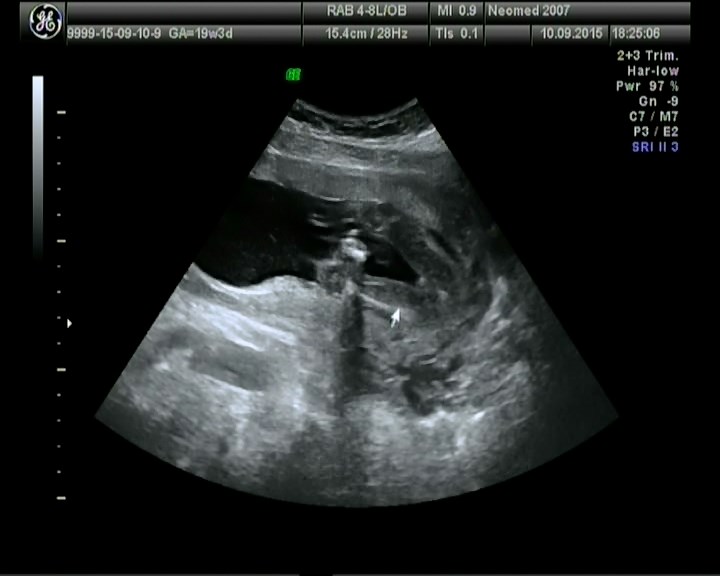

На второе скрининговое узи сходили вместе с мужем к очень хорошему узисту,с отличной аппаратурой.В Мед.Центр Мать и Дитя,мы были в вросторге и от клиники и от узиста,все четко,померял даже каждую почку,печень,мочевой,посмотрел камеры сердца,доплером посмотрел кровоток и даже записал нам диск на память.

Много фоточек вытянула из видео)